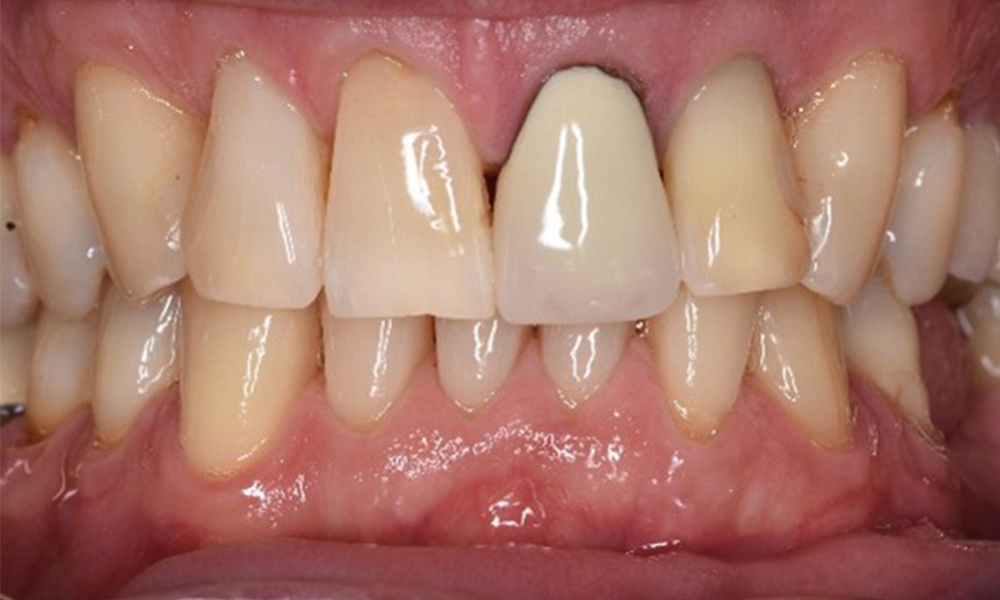

In the medical history, the 55-year-old patient states that he has no systemic disease and is not taking any medication. The patient’s lifestyle is similarly unremarkable. The patient has a few tooth restorations and two implants (2nd and 4th quadrants). On the basis of current findings, gingivitis is identified in an otherwise stable periodontal condition on the reduced periodontium (stage III, grade A).

Previous treatments: dental restorations (non-precious metal/ceramic blend), two implants (2nd, 4th quadrants)

The patient has no particular risk factors with specific dental implications. The key factor, therefore, is the requirement in terms of oral health. In this respect, good oral health is evident with stable, reduced periodontium. Should evidence of an increase in probe depth compared with the baseline, combined with diffuse bleeding, be found at a check-up appointment, diagnosis using X-ray imaging (dental X-ray) should be undertaken in order to identify peri-implant bone loss at an early stage and intervene accordingly.